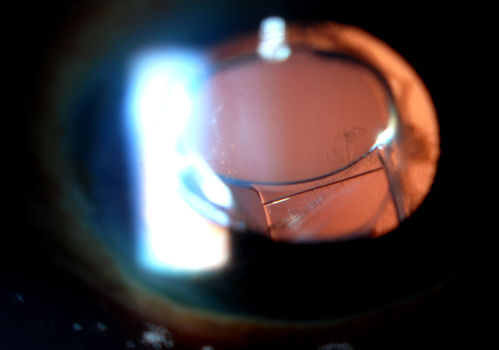

Accordioning Crystalline Lens with loss of Posterior Capsule

71-year old male complains of blurred vision in the left eye. VA 20/40, right eye and 20/400, left eye without correction. Slit lamp exam shows Crystalline lens, both eyes. Right eye IOL is aligned and centered. Left eye shows an accordion of the crystalline lens. Retro Illumination shows the IOL bent inward in the left eye. There was a 6-diopter difference of astigmatism between the right and left eye. Patient will have surgery to correct the issue.